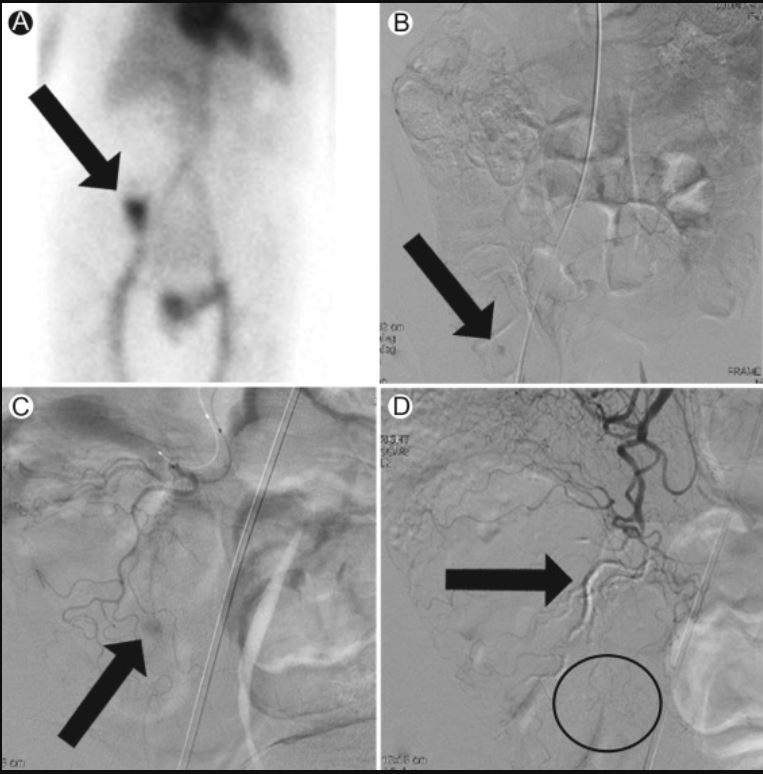

✅tagged RBC scan (pic2⬇️ = LGIB)

Localizing Scans for a LGIB (Nice job IR😍)

🌟Tagged RBC:⬆️radiotracer uptake in cecum = active🩸in area

🌟Angio of SMA: active🩸in R colon

🌟Angio of ileocolic artery: locates extravasation area

🌟Post-embolization: cast fills culprit ileocolic branch▶️🩸resolved(!)